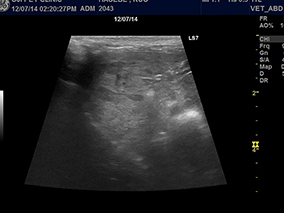

半年前から肝酵素の上昇が見られており、徐々に食欲が落ちてきたワンちゃんの肝臓の超音波所見です。

肝臓が全体的に粗雑になっており、滑らかさがなくなっていました。高齢なのでお腹を開けての肝臓のバイオプシーは負担がかかってしまう、負担をなるべく軽くしてあげたい、との飼い主様のご希望で当院の腹腔鏡下肝バイオプシーを実施しました。